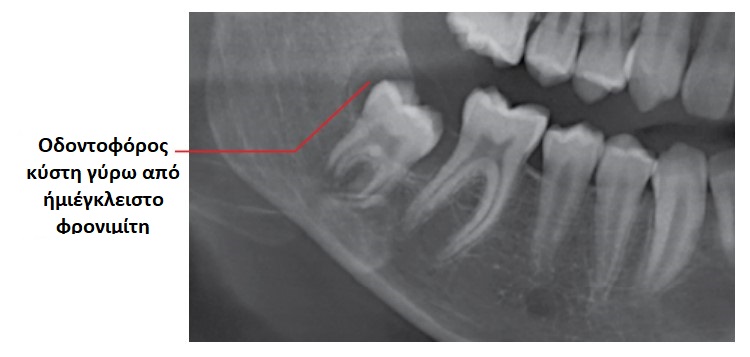

Οι οδοντοφόρες κύστεις είναι οι δεύτερες σε συχνότητα εμφάνισης οδοντογενείς κύστεις, και αποτελούν τις πιο κοινές αναπτυξιακές κύστεις των γνάθων.

Εξ ορισμού η οδοντοφόρος κύστη προσφύεται στον αυχένα και περιβάλλει τη μύλη ενός εγκλείστου δοντιού.

Είναι σημαντικό η διάγνωση “οδοντοφόρος κύστη” να μην τίθεται αποκλειστικά και μόνο με βάση τα ακτινογραφικά ευρήματα, καθώς στην περίπτωση αυτή οδοντογενείς κερατινοκύστεις και μονόχωρα αδαμαντινοβλαστώματα που εμπλέκουν έγκλειστα δόντια είναι δυνατό να διαγνωστούν λανθασμένα ως οδοντοφόρες κύστεις.

Συνήθως τα συμπτώματα απουσιάζουν, ενώ η καθυστερημένη ανατολή ενός δοντιού είναι η συχνότερη ένδειξη ύπαρξης οδοντοφόρου κύστης. Οι ασθενείς είναι δυνατό να παρατηρήσουν αργά αυξανόμενη διόγκωση. Μια κύστη μπορούσε να φτάσει τα 4-5 εκ. σε διάμετρο σε χρονικό διάστημα 3-4 ετών. Η κύστη είναι δυνατό να φτάσει σε μεγάλες διαστάσεις, ενώ σπάνια φτάνει σε τέτοιο μέγεθος ώστε να προδιαθέτει σε παθολογικό κάταγμα. Σε περίπτωση επιμόλυνσης, η κύστη μπορεί να γίνει επώδυνη.

Η αφαίρεση των εμπλεκόμενων δοντιών και η εκπυρήνιση των μαλακών μορίων αποτελεί οριστική θεραπεία στις περισσότερες των περιπτώσεων. Όταν οι κύστεις επεκτείνονται σε μεγάλο τμήμα της κάτω γνάθου, μια αποδεκτή θεραπευτική προσέγγιση είναι η μαρσιποποίηση ή στοματοποίηση της κύστης, ώστε να επιτραπεί η αποσυμπίεση και η επακόλουθη σμίκρυνση της βλάβης, μειώνοντας έτσι την έκταση της επέμβασης για εκτομή της βλάβης, που ενδεχομένως να χρειασθεί να γίνει σε δεύτερη φάση.